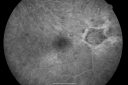

Diabetic and Pseudophakic Cystoid Macular Edema Late FA569 views56-year-old woman has diabetic retinopathy in both eyes and macular edema. She is recently pseudophakic. OD 20/80, OS 20/200. Nov 11, 2010

Diabetic and Pseudophakic Cystoid Macular Edema Late FA fellow Eye641 views56-year-old woman has diabetic retinopathy in both eyes and macular edema. She is recently pseudophakic. OD 20/80, OS 20/200. Nov 11, 2010

Diabetic and Pseudophakic Cystoid Macular Edema Late FA - Leakage Macular and Nerve555 views56-year-old woman has diabetic retinopathy in both eyes and macular edema. She is recently pseudophakic. OD 20/80, OS 20/200. Nov 11, 2010

Diabetic and Pseudophakic Cystoid Macular Edema FA Fellow Eye766 views56-year-old woman has diabetic retinopathy in both eyes and macular edema. She is recently pseudophakic. OD 20/80, OS 20/200. Nov 11, 2010

Diabetic and Pseudophakic Cystoid Macular Edema Pretreatment Mid FA626 views56-year-old woman has diabetic retinopathy in both eyes and macular edema. She is recently pseudophakic. OD 20/80, OS 20/200. Nov 11, 2010

Diabetic and Pseudophakic Cystoid Macular Edema Pretreatment Mid FA641 views56-year-old woman has diabetic retinopathy in both eyes and macular edema. She is recently pseudophakic. OD 20/80, OS 20/200. Nov 11, 2010

Diabetic and Pseudophakic Cystoid Macular Edema Pretreatment Early FA658 views56-year-old woman has diabetic retinopathy in both eyes and macular edema. She is recently pseudophakic. OD 20/80, OS 20/200. Nov 11, 2010

Diabetic and Pseudophakic Cystoid Macular Edema Pretreatment early FA645 views56-year-old woman has diabetic retinopathy in both eyes and macular edema. She is recently pseudophakic. OD 20/80, OS 20/200. Nov 11, 2010

Diabetic and Pseudophakic Cystoid Macular Edema Pretreatment Fundus Photo740 views56-year-old woman has diabetic retinopathy in both eyes and macular edema. She is recently pseudophakic. OD 20/80, OS 20/200. Nov 11, 2010

Diabetic and Pseudophakic Cystoid Macular Edema Pretreatment Fundus Photo870 views56-year-old woman has diabetic retinopathy in both eyes and macular edema. She is recently pseudophakic. OD 20/80, OS 20/200. Nov 11, 2010

Diabetic and Pseudophakic Cystoid Macular Edema Pre Treatment659 views56-year-old woman has diabetic retinopathy in both eyes and macular edema. She is recently pseudophakic. OD 20/80, OS 20/200. Nov 11, 2010